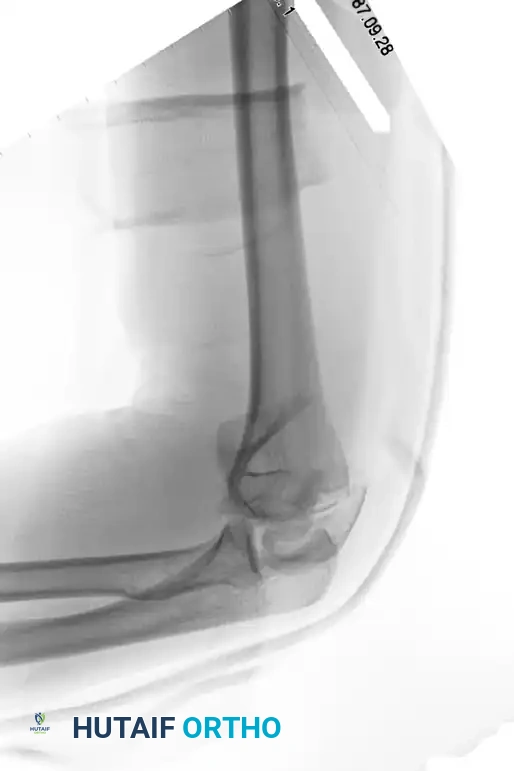

Supracondylar fracture intraarticular

Preoperative imaging of a supracondylar fracture with intraarticular extension.